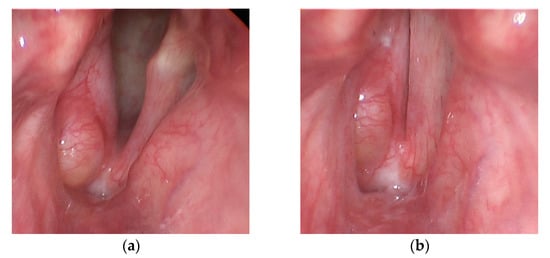

A 78-year-old male was recruited for this study who had previously (12 years prior) undergone a unilateral, right vocal fold hemilaryngectomy for the treatment of laryngeal cancer (T2bN0M0 squamous cell carcinoma). An adipose tissue implant, taken from the periumbilical region, was injected to medialize the right vocal fold and facilitate glottal closure as the left vocal fold oscillated during phonation. The individual follows up regularly with his treating laryngologist for cancer surveillance and to assess vocal function, which includes laryngeal videoendoscopic examinations with stroboscopy. Figure 1 displays endoscopic images of the individual’s larynx in an abducted and adducted state. Video S1 (Supplementary Materials) displays a segment from the videostroboscopic examination as the individual produces voice at a comfortable and higher-than-comfortable pitch level. According to clinical notes, the individual exhibited normal pliability and mucosal wave of the left vocal fold and diminished pliability and mucosal wave of the right vocal fold, consistent with expectations following the hemilaryngectomy and reconstruction. Complete glottal closure was observed during phonation with entrained vocal fold oscillation, mild phase asymmetry, and significantly reduced amplitude of the right vocal fold. There was no evidence of recurrent laryngeal disease.

Figure 1. Endoscopic images of the larynx from the videostroboscopy examination of the participant who had previously undergone a unilateral (right vocal fold) hemilaryngectomy to treat laryngeal cancer. Shown are snapshots of the vocal folds in states of (a) abduction and (b) adduction.